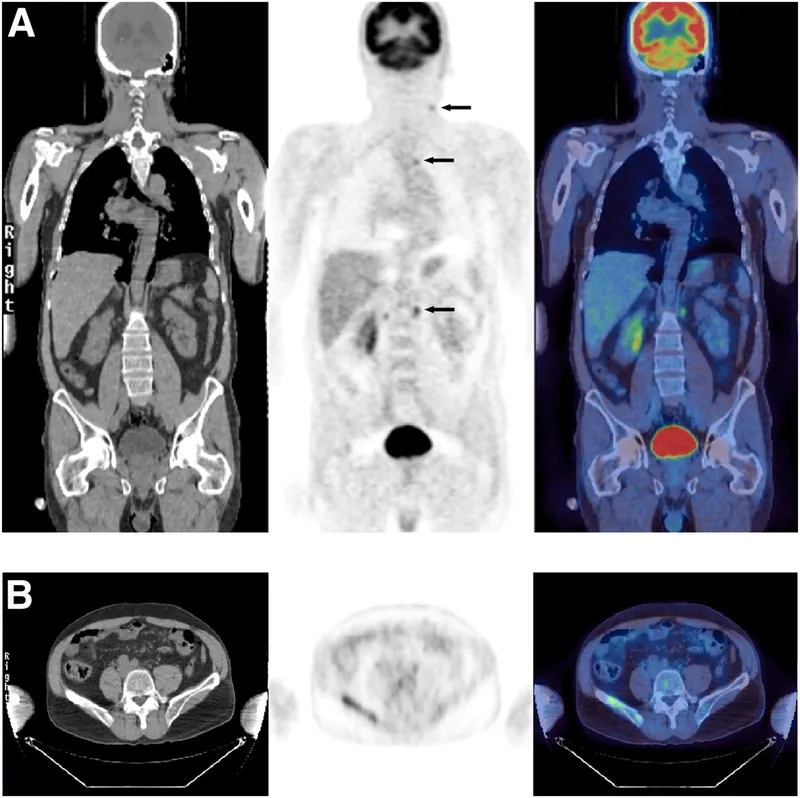

Oncology (Primarily $^{18}F-FDG$ PET/CT):

- Core Uses: Staging, restaging, therapy response, recurrence, biopsy guidance.

- Key Metric: Standardized Uptake Value (SUV); $SUV_{max}$ reflects max tumor metabolic activity. ↑ uptake in active tissues.

- Common Cancers: Lymphoma, lung, colorectal, breast, melanoma, H&N.

⭐ FDG-PET/CT often detects occult metastases missed by conventional imaging, changing management in up to 30% of cases.

- Neuroendocrine Tumors (NETs): $^{68}\text{Ga-DOTATATE}$ PET/CT.